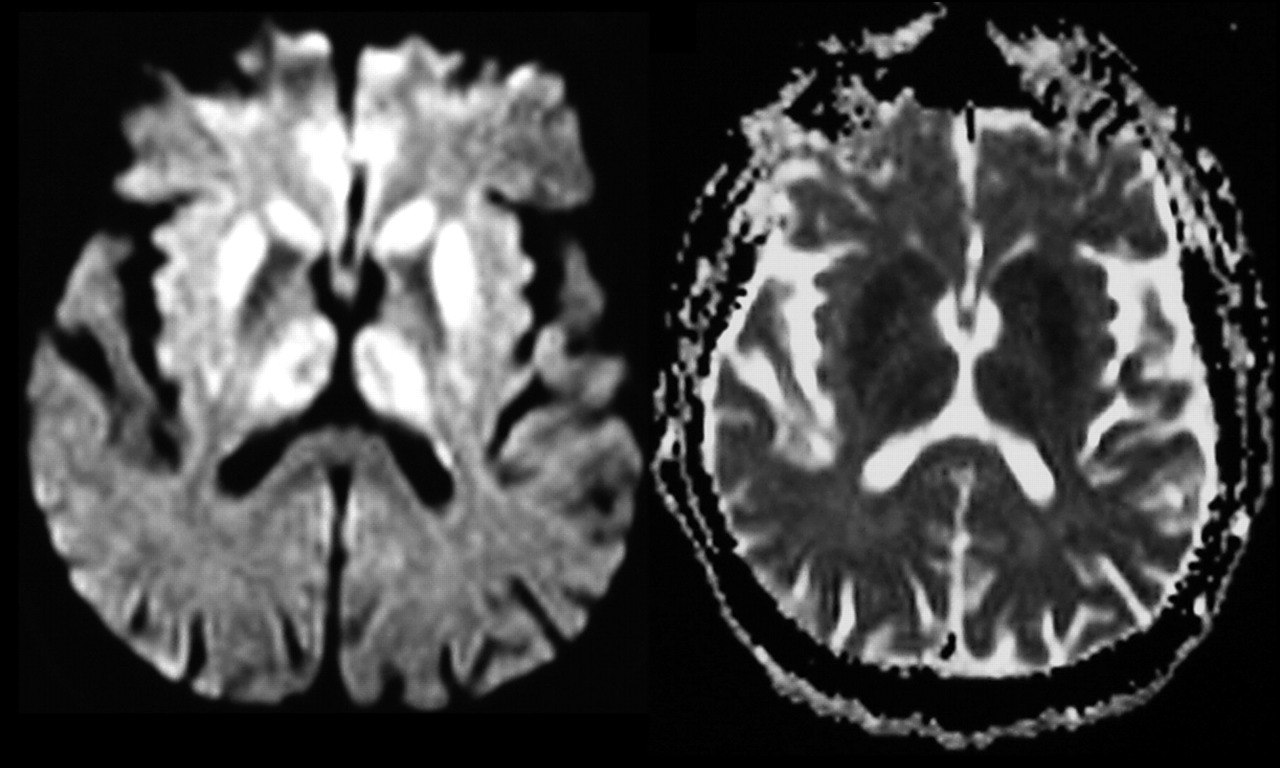

La CJD è una malattia rara causata da una proteina anormale nel cervello chiamata prione.

I prioni si trovano naturalmente nel cervello e di solito sono innocui, ma quando si ammalano o si ripiegano male, influenzeranno i prioni vicini per deformarsi, portando al deterioramento del tessuto cerebrale e alla morte.

La malattia è incurabile in quanto una volta che un prione viene infettato, continuerà a contagiare altri prioni senza alcun trattamento in grado di fermare questo progresso.

Uno studio statunitense ha ipotizzato che una proteina spike mal ripiegata potrebbe a sua volta creare una regione prionica mal ripiegata che potrebbe essere in grado di interagire con prioni sani per causare danni, portando alla malattia CJD.